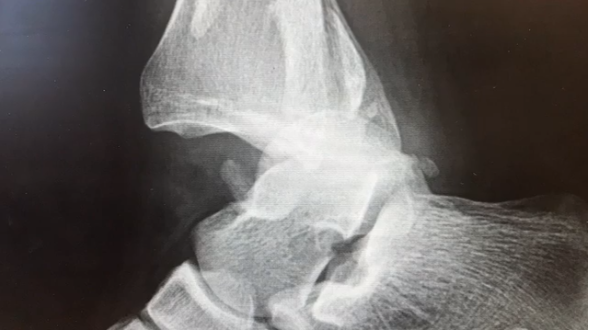

Discover the latest data supplements from Foot & Ankle International (FAI), the industry-leading journal for clinically-oriented research articles and therapeutic approaches in foot and ankle scholarship.